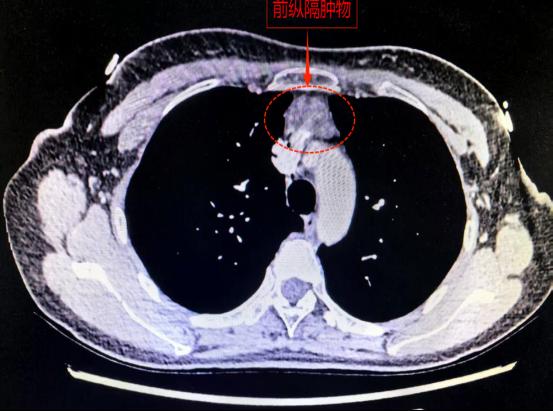

30岁的黄女士就面临着这样的挑战。一年前她在体检中发现前纵膈肿物,近期复查显示,该肿物已显著增大至3.5厘米。且肿物位置十分“刁钻”,紧贴胸骨与心脏之间,并与重要血管紧密相邻。若不及时处理,肿物可能继续增大,进而压迫心脏及大血管,甚至侵犯周围组织。

胸部CT显示前纵隔肿物紧贴心脏大血管